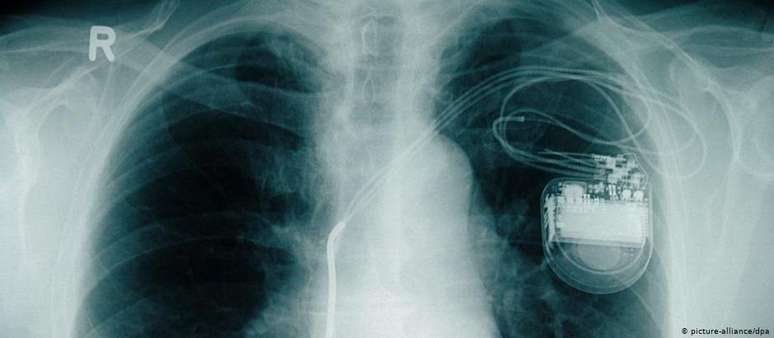

Marca-passo observado em imagem de raio-x: milhões de pessoas no mundo vivem com o implante

Milhões de pessoas no mundo todo vivem com marca-passos, pequenos implantes elétricos que ajudam a regular os batimentos cardíacos após uma doença crônica ou aguda. Porém, apesar dos avanços tecnológicos, as baterias utilizadas são muitas vezes rígidas e volumosas, eventualmente tendo que ser substituídas várias vezes.